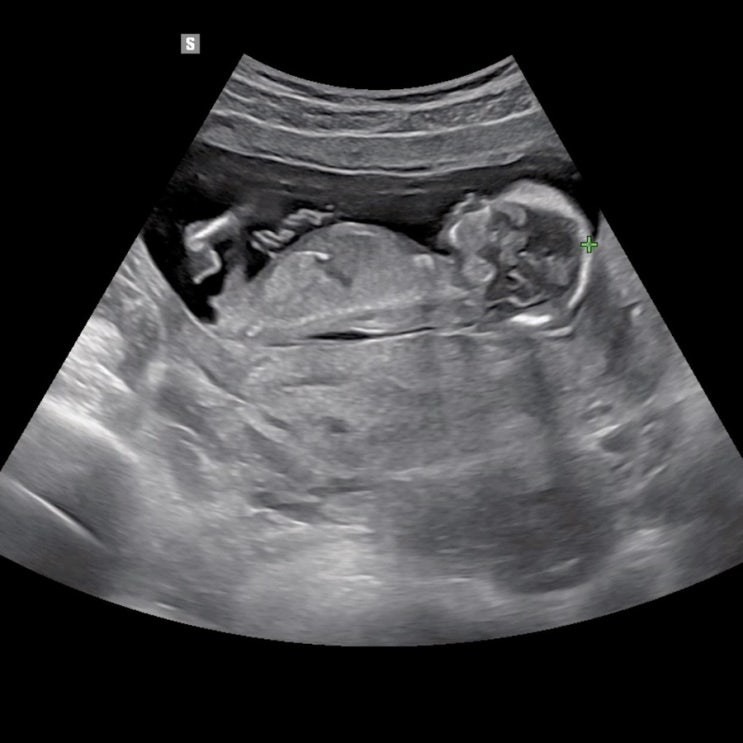

14주 성별 확인 알려주는 시기 딸 초음파